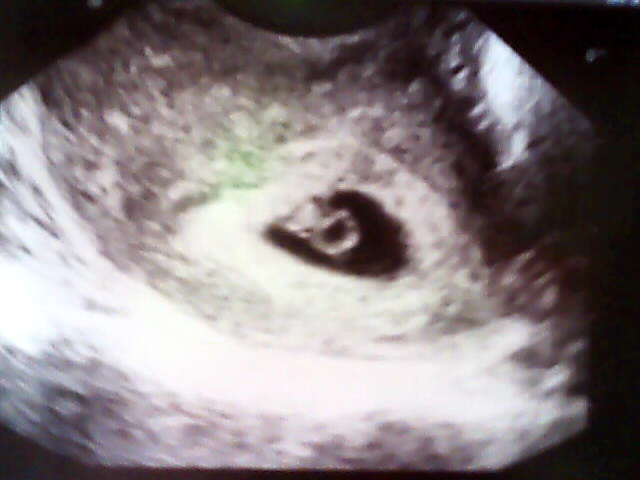

Autor: veveruska 10.3.2014 v 16:57

Ahojky holky,tak dneska jsem díky bolestem v podbříšku byla na kontrole a vše je ok mimi už je krásně vidět má necelých 7mm a srdíčko už taky krásně bije,dám sem fotku pro povzbuzení a všem vám držím palečky...jinak jsem dneska 6+3

No taky se divím se koukni na tu první fotku ta je z 5+3 a ta druhá z dneška a to je 6+3 za ten týden už to je krásně vidět a srdíčko bylo taky krásně vidět...mimochodem mám termín podle ultrazvuku přesně na 7. narozeniny mého druhého syna